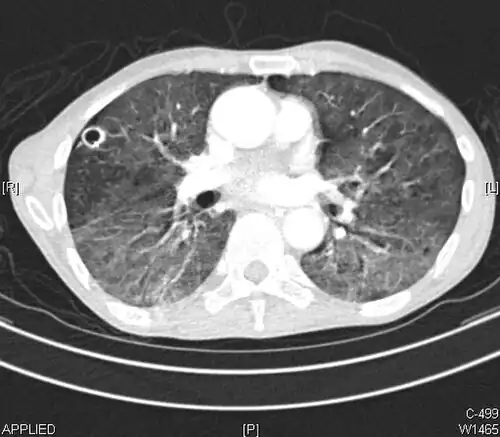

CT image showing patchy areas of ground-glass opacities representing pulmonary edema.